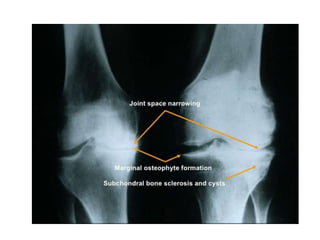

0 – No features of osteoarthritis

1 – Doubtful, osteophyte of doubtful significance

2 – Minimal, definite osteophyte but joint space

unimpaired

3 – Moderate, moderate diminution of joint space

4 – Severe, Joint space severely impaired with sclerosis

of sub-chondral bone

* Kellegren & Lawrence Scale for Osteoarthritis